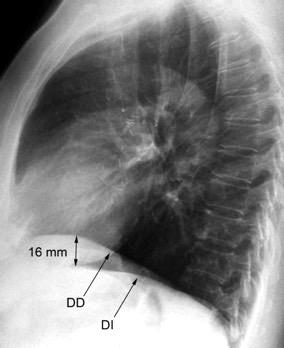

Diafragma izquierdo +/-16mm El ligamento pulmonar izquierdo (LPI) puede interrumpir la interfase normal pulmonar-diafragma obliterando un pequeño segmento

Proto AV,. The left lateral radiograph of the chest. Part One. Med. Radiogr. Photogr.1979.